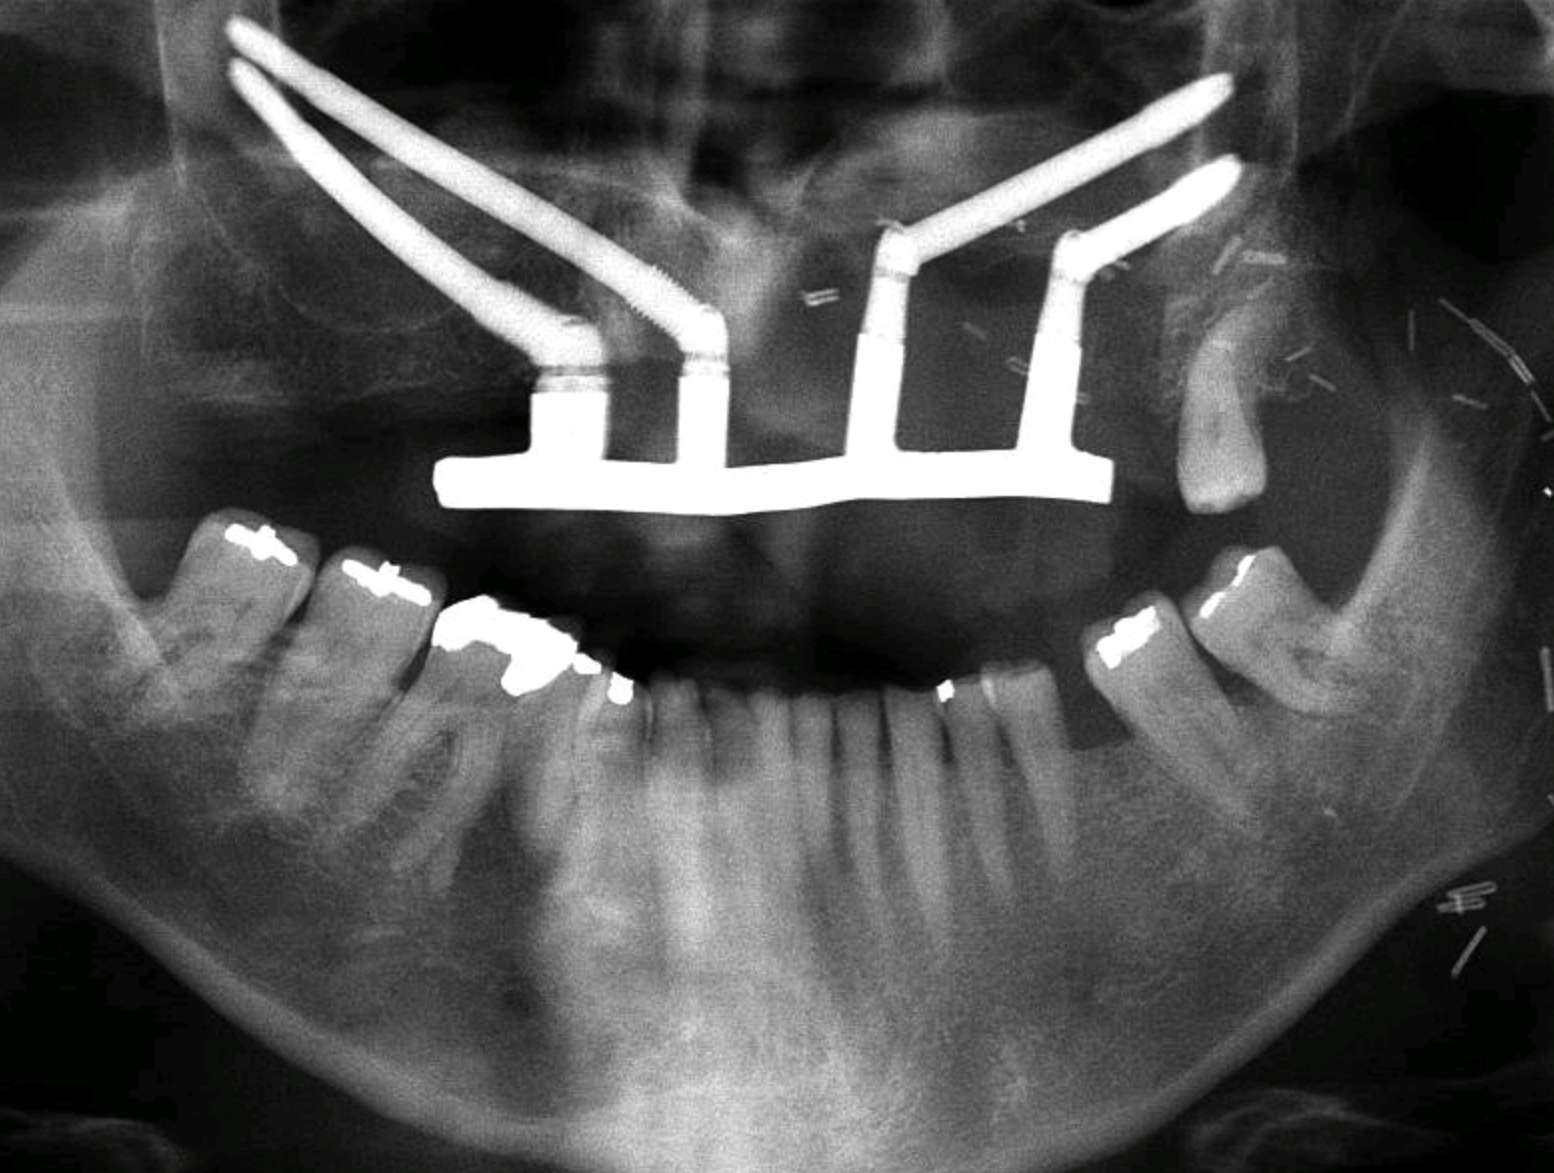

Fixed zygomatic implant-retained prosthesis following ZIP-Flap reconstruction

The Zygomatic Implant Perforated (ZIP) Flap combines free flap reconstruction with simultaneous intraoperative zygomatic implant placement — enabling fixed dental rehabilitation within weeks of ablative surgery for low-level maxillary malignancy.

First described in 2017 and supported by a prospective cohort of 35 consecutive cases, the ZIP Flap is rapidly becoming international standard of care. A dedicated training programme operates annually at Keele Medical School.